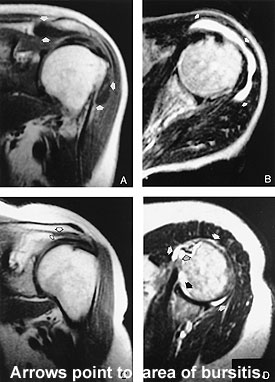

A 55-year-old housemaid complained to her doctor of pain at the tip of the right shoulder. It started a few weeks ago with no predisposing trauma. It is worse at the initial stage of abducting her right arm, or when she is carrying a heavy object like a full bucket. The doctor examined her and confirmed the painful abduction of the right shoulder. There was no obvious abnormality on the plain radiograph of the region. The doctor diagnosed subacromial bursitis and recommended rest and analgesics.

The supraspinatus muscle tendon is separated from the coracoacromial ligament, the acromion, and the deltoid muscle by the subacromial bursa. When this bursa is inflamed, abduction of the arm will be painful.